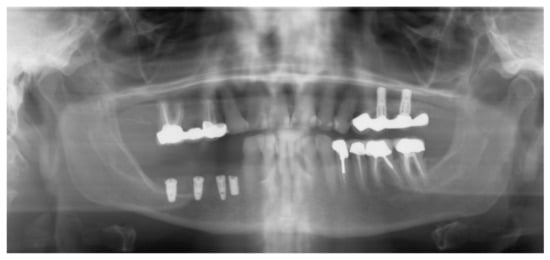

Figure 16.

Panoramic radiograph showing the implants in place.